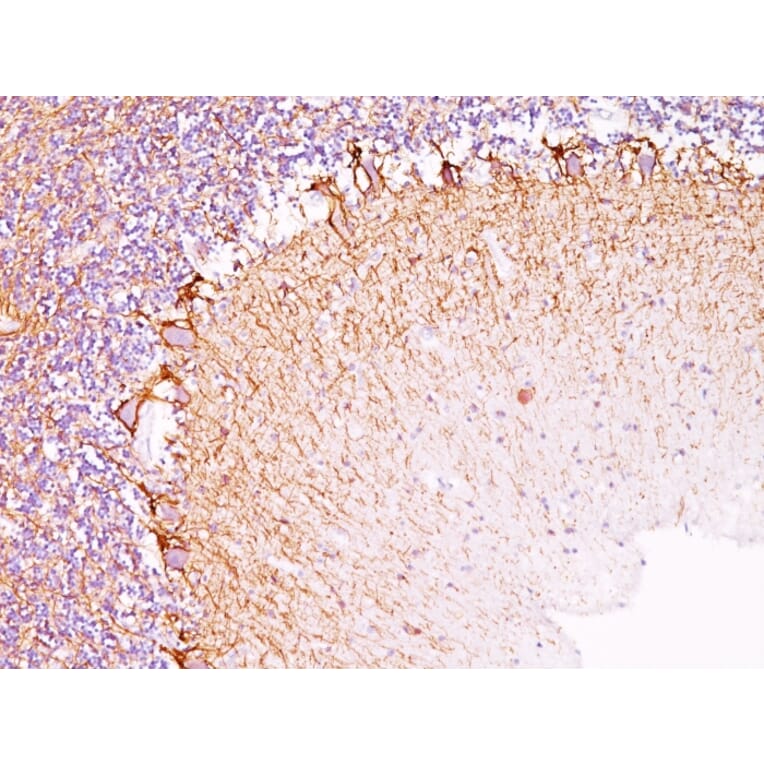

This antibody reacts with a 68kDa protein, identified as light sub-unit of neurofilaments (NF-L). Neurofilaments make up the main structural elements of axons and dendrites and are found in neurons, peripheral nerves, and sympathetic ganglion cells. Neurofilaments consist of three major subunits with molecular weights of 68kDa (NF-L), 160kDa (NF-M) and 200kDa (NF-H). Anti-neurofilament stains a number of neural, neuroendocrine, and endocrine tumors. Neuromas, ganglioneuromas, gangliogliomas, ganglioneuroblastomas, and neuroblastomas stain positively for anti-neurofilament. Neurofilaments are also present in paragangliomas as well as adrenal and extra-adrenal pheochromocytomas. Carcinoids, neuroendocrine carcinomas of the skin, and oat cell carcinomas of the lung also express neurofilament.

IF, Flow Cytometry, IHC-P

IF: 1-2 µg/ml, Flow Cytometry: 1-2 µg/million cells, IHC-P: 1-2 µg/ml